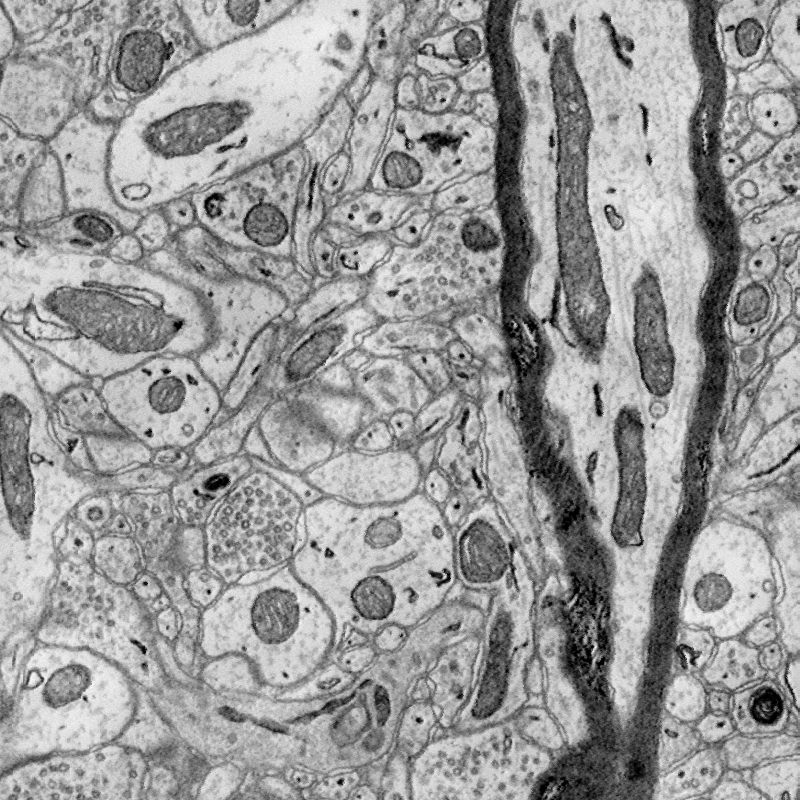

Below are two images: the first shows an original EM slice, and the second shows the output of the 3D Sobel operator.

We also added the norm as a parameter and tested a modified Sobel operator with replaced by for various values. Finally, we added the ability to binarize the output of the 3D Sobel operator using mean and standard deviation-based thresholds.

Notice clear remnants of closed curves, many with circular eccentricity. We are working on an algorithm to integrate around points on the closed curves and output a single stable center point. Our main goal is to detect and extract feature patches for registering regions of the connectome. We develop and energy function that can be optimized that outputs many of these center points. From these, a sparse graph can be constructed, and then further dense modeling of EM blocks and connectome regions. We will extract a feature vector based on cell regions, neurons, axons and synapses. We first build a graphical model based on statistically stable regions learned from experiments on large volumes of EM data.